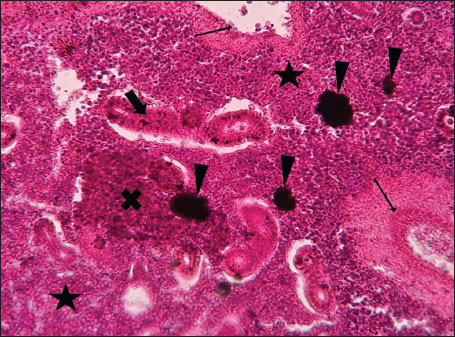

Histopathological examination of the kidney tissues of L. sceleratus revealed multiple alterations. Prominent melanomacrophage centers (MMCs), necrotic areas, dilatation of Bowman’s capsules, and vacuolar degeneration were observed (Fig. 1), associated with interstitial lymphohematopoietic tissue (Fig. 2). Dilated and congested blood vessels and extensive MMCs were also noted (Fig. 3). Renal degeneration surrounding lymphohematopoietic tissue, large clusters of MMCs, and thickened, congested vessel walls within fibrotic areas were evident (Fig. 4). Atrophic renal degeneration with necrotic and vacuolar changes was observed (Fig. 5). Severe inflammatory infiltration of lymphatic cells and granulomas with necrotic centers, surrounded by fibrous tissue, was detected (Figs. 67).

Fig. 3. Histopathology of the kidney in an adult L. sceleratus showing dilated and congested blood vessels (star) and severe MMC proliferation (head arrows). ×40 H&E.

The present study revealed pronounced histopathological alterations in both the kidneys and gills of L. sceleratus collected along the Libyan coast. Kidney lesions, including tubular degeneration, Bowman’s capsule dilatation, proliferation of MMCs, vascular congestion, and inflammatory infiltration, were associated with histologically detected structures, but no parasitic structures were detected in kidney tissues. These patterns are commonly reported in marine teleosts exposed to chronic environmental stressors (Ali et al., 2014; Steinel and Bolnick, 2017; Carreras-Colom et al., 2022). These lesions should be interpreted as descriptive indicators of physiological stress rather than direct evidence of chemical pollution or causality, consistent with Flores-Lopes and Thomaz (2011). Vascular abnormalities, including congestion and thickened vessel walls, were evident, which may reflect chronic circulatory disturbances or inflammatory responses rather than acute toxicity (Bernet et al., 1999; Thophon et al., 2003). Interstitial lymphohematopoietic tissue, inflammatory cell infiltration, and granulomatous formations suggest that parasitic or microbial challenges could contribute to renal lesions. Despite these histopathological changes, the sampled fish appeared healthy at capture, demonstrating the potential physiological resilience of marine teleosts. Fish kidneys possess compensatory mechanisms, and gills serve critical osmoregulatory and excretory functions, allowing survival despite structural alterations (Evans et al., 2005; Hwang et al., 2011; Hinton et al., 2018; Leone et al., 2018). Gradual development of renal lesions likely enables adaptation without acute organ failure.